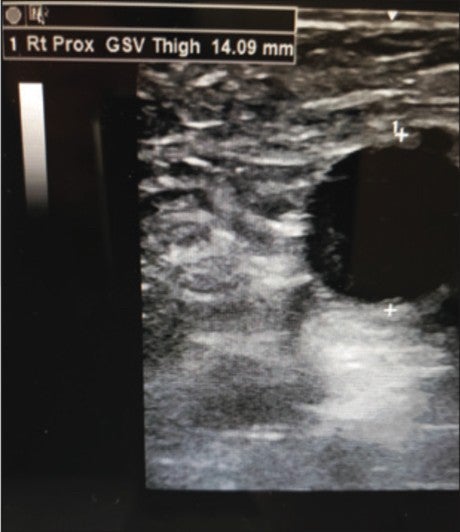

Vein diameters measured 14.1mm in the proximal GSV (Figure 3) and 12.2mm in the mid-GSV (Figure 4). CEAP class of 5.

Figure 3. Pre-Varithena Treatment Rt. Proximal GSV. Vein diameter: 14.09 mm